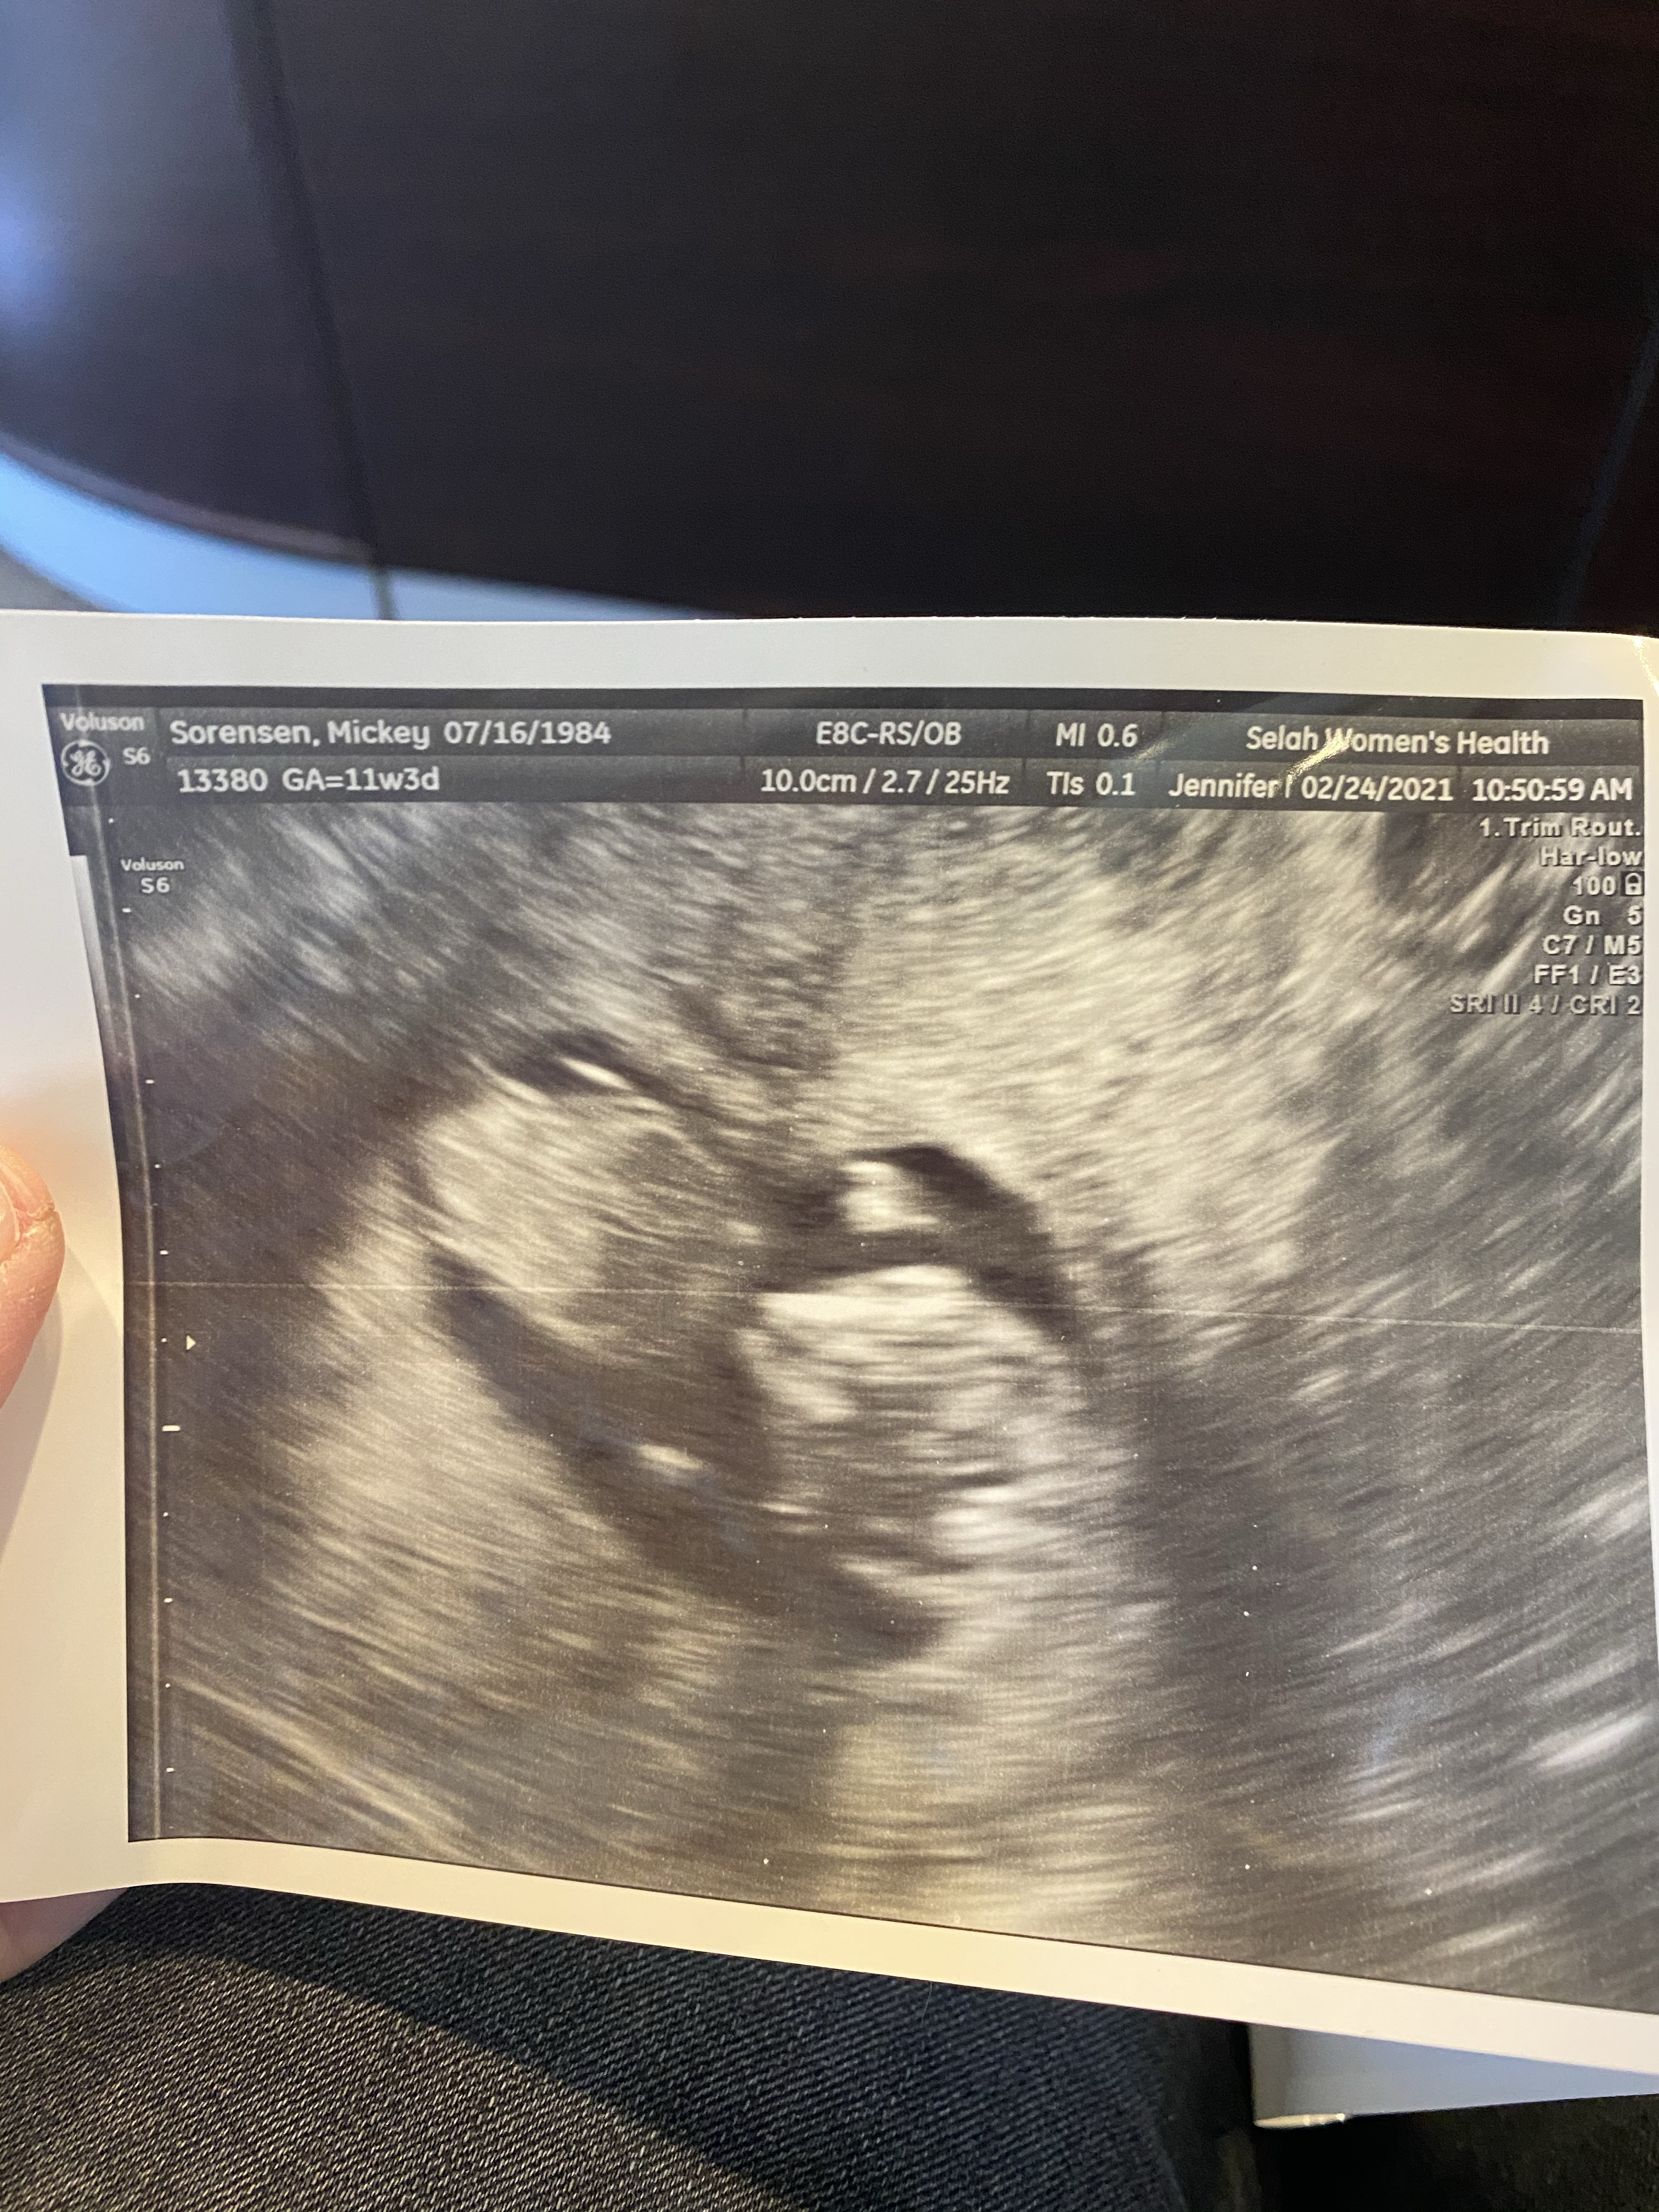

Well, we are three weeks away from welcoming our last baby into the fam and it feels like I have both been pregnant forever and also that this year has flown by. A few days after Christmas I got the faintest positive test. After tracking and testing for two and half years, this was a real surprise. We sort of had given up? That this would happen? I just felt like our family wasn’t complete, I even looked into foster care for awhile. Nothing felt right. I had several positive tests over the years but the lines would get darker for a few days, and then fade away. This time however, the lines got darker everyday and I had this glimmer of hope that this might be it. After three weeks I finally told Jazz, lol. He was… shocked. We had our first ultrasound and saw a tiny little flicker of a heartbeat.

The first trimester was a mixture of so much hope and so much worry. We have had many sad ultrasounds over the years and every time we went in for another scan, I thought I was going to be sick in the waiting room. Every time though, that little flicker was still there, the baby looked bigger and measured right on track. I spent many mornings and afternoons on the couch, sick and tired but really thankful.